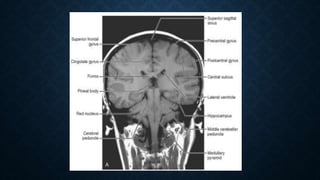

HUMAN BRAIN :- REALLY A

MAZE !!!!!!

  